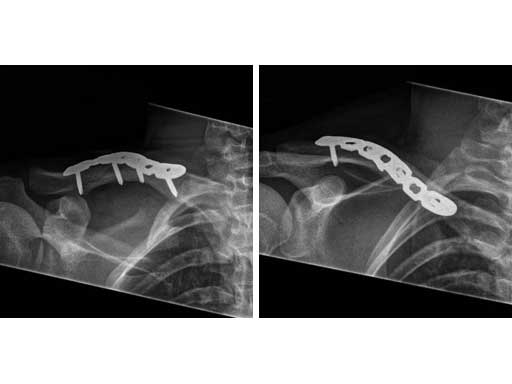

A 21-year old male fell on the right shoulder when playing soccer. He sustained a cavicular shaft fracture type 06 A3 (OTA classification) with dislocation of shaft width and shortening of around 2 cm.

Fig 4ab X-rays 9 months postoperatively.